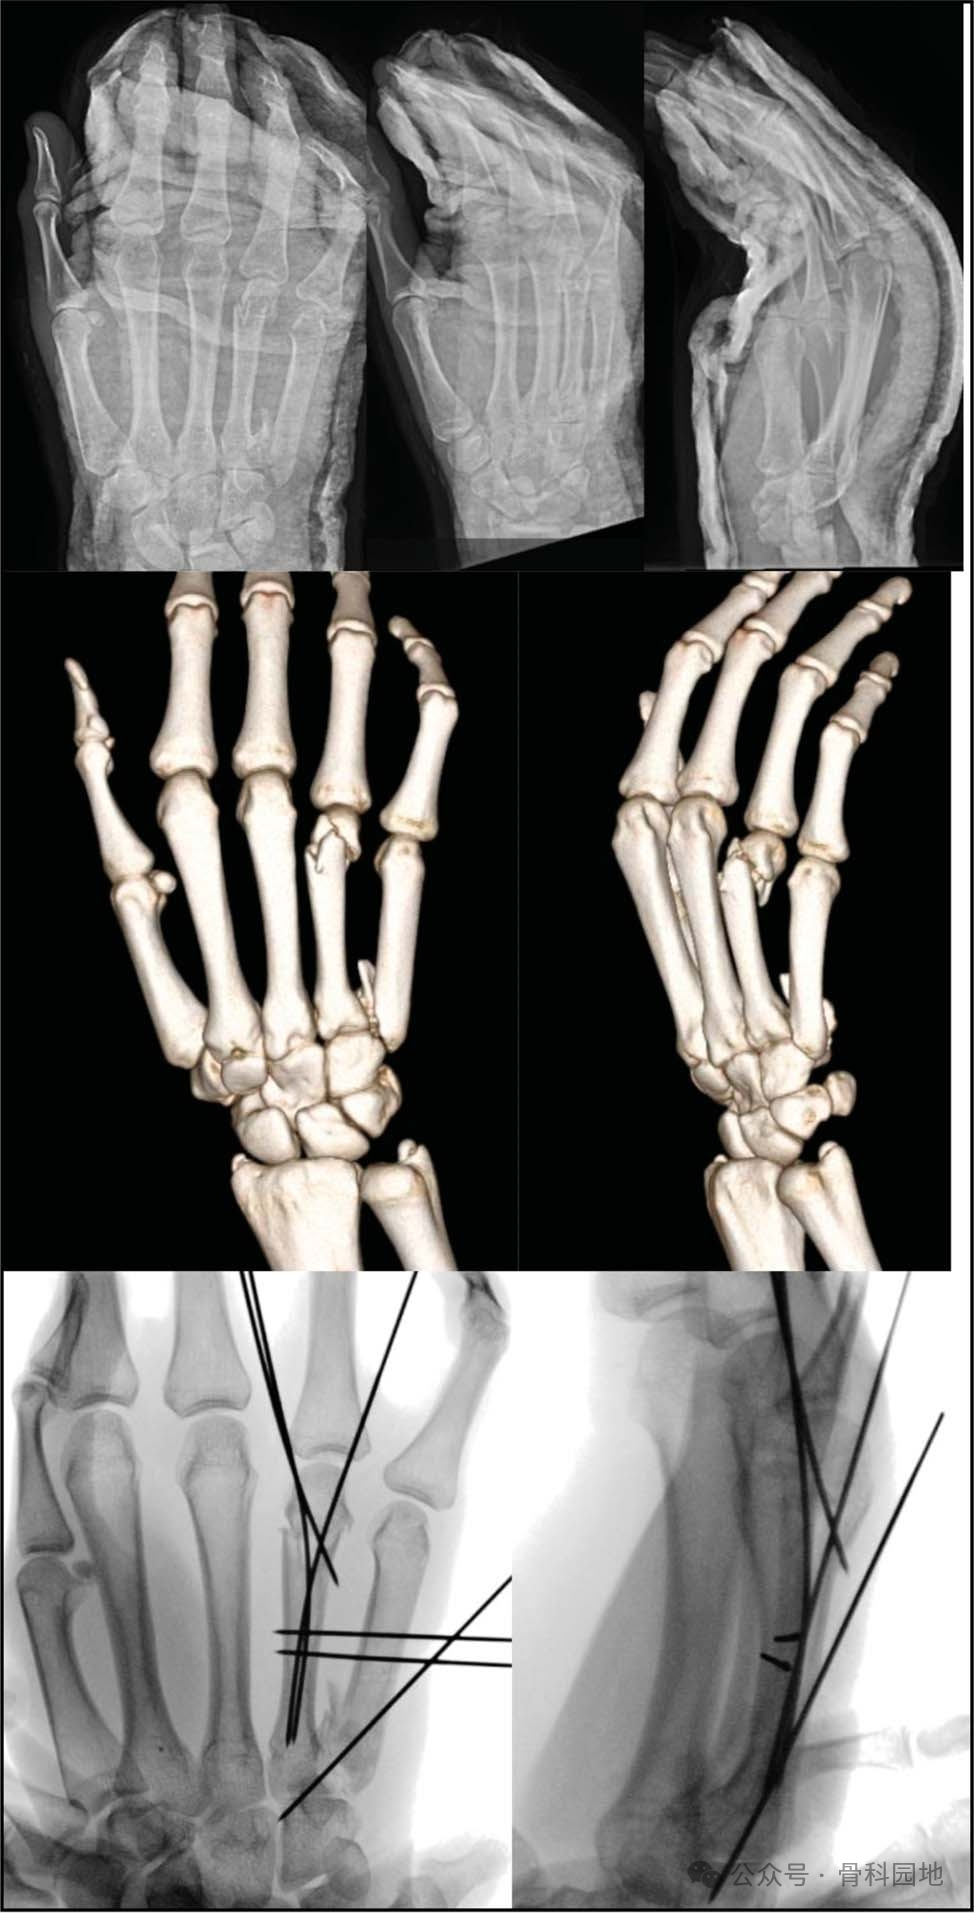

三、掌骨干骨折

手术治疗,有几种不同的技术可使用,包括克氏针固定(最常见)、单独骨折间螺钉、钢板和螺钉、髓内固定或外固定。

髓内螺钉可以是一种安全的技术,即使对于粉碎性或螺旋型骨折,也可以最大限度地减少手术时间。

最后一个需要考虑的固定选择是外固定架的应用,尽管这种方法不太常用。适用的适应症包括开放性骨折、软组织缺损、骨髓炎或节段性骨缺损。